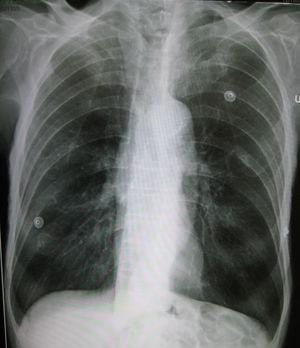

| A lateral chest x-ray of a person with emphysema. Note the barrel chest and flat diaphragm. | |